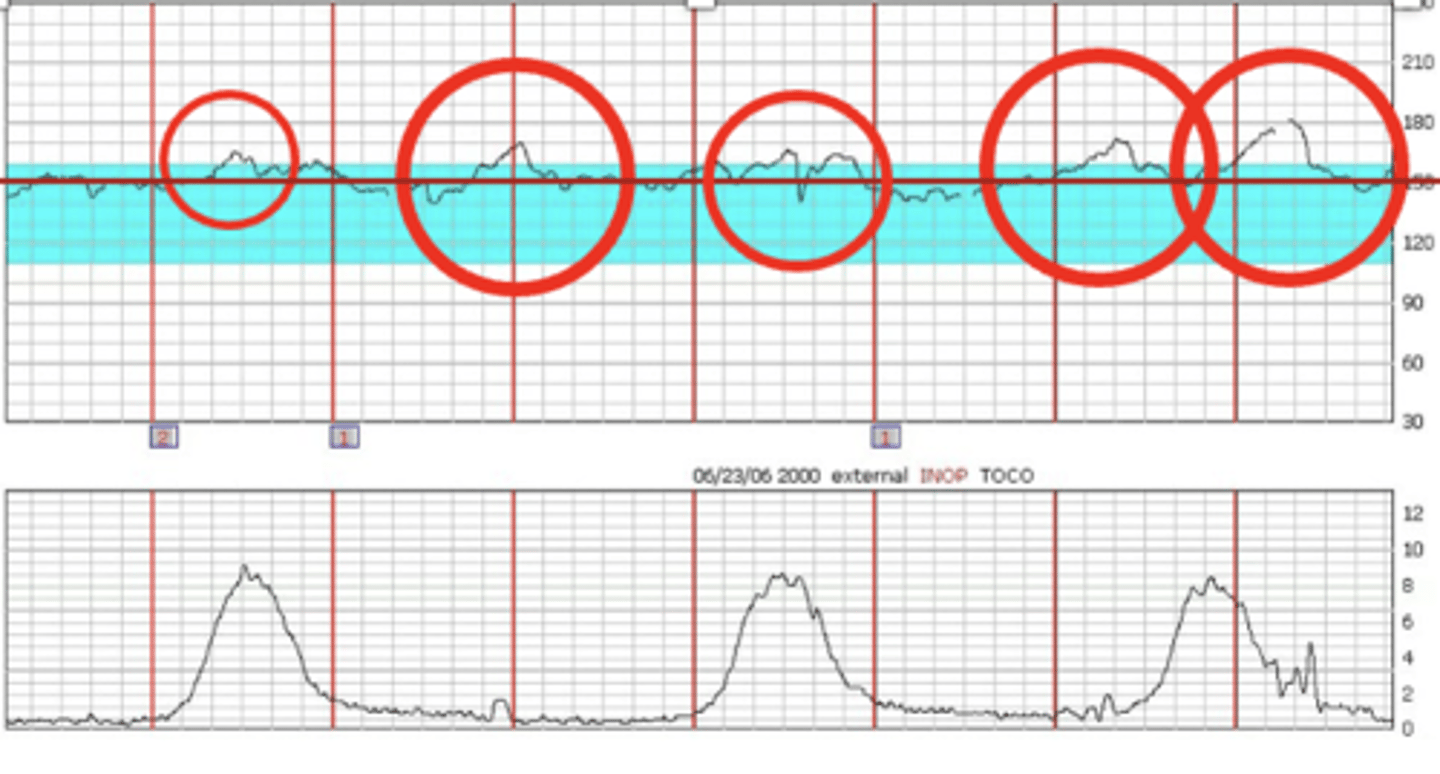

Nonstress test

Determines fetal activity

-FHR monitored for 20-30 and tracing is observed for signs of fetal activity and concurrent acceleration in FHR

-Makes sure baby is getting enough oxygen from placenta

reactive nonstress test

2 accelerations in 20 minutes each lasting 15 secs and 15 bpm above baseline

-Accelerations happen when baby moves

Contraction stress test

Identify jeopardized fetus that is stable at rest, but compromised with stress

-Contractions stimulated with nipple stimulation or oxytocin until 3 contractions lasting 40-60 sec in 10 mins)

-FHR monitored

-Toco (contraction monitor) senses when mom contracts

-Tracing observed to see how baby responds to contractions

Negative contraction stress test

(Normal) A negative result is represented by no late decelerations of fetal heart rate (FHR).